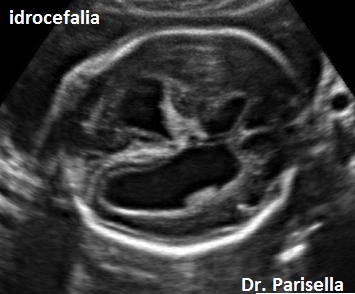

-         Anomalie del SNC: lipoma del corpo calloso, idrocefalia, malformazione di Chiari, encefalocele, ipoplasia del verme cerebellare, megacisterna magna, ipoplasia unilaterale del cervelletto.